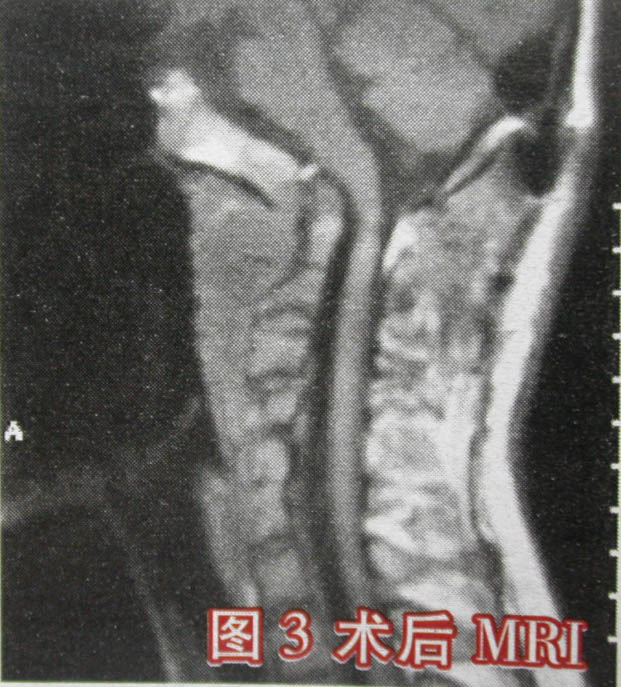

近日,北京大学第三医院骨科颅椎外科专业组采用创新术式,成功地为1例枕大孔区(颅椎区)复杂畸形,并继发严重寰枢关节脱位的19岁患者实施了手术治疗。患者入院时寰枢关节已呈完全脱位状态,枢椎齿突上移入枕大孔(图1),脊髓受压出现严重功能受损(图2),患者已有全身瘫痪、呼吸功能不全表现。该专业组王超主任医师等采用经口咽入路寰枢关节松解复位术和后路枕颈固定植骨融合术,使患者寰枢关节得以复位固定,其受压脊髓得到彻底减压。术后患者已恢复行走功能,日前已出院。